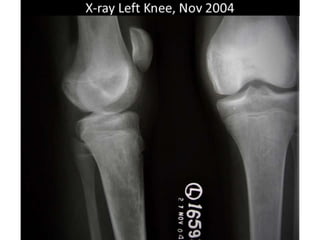

The document presents a detailed case study of a patient with transient osteoporosis of the hip (TOH) and spontaneous osteonecrosis of the knee (SONK) treated at Choithram Hospital & Research Centre in India. Over 20 years, the patient experienced multiple episodes of TOH and SONK with no history of trauma or co-morbidities, resulting in resolutions and recurrences of conditions. The information is intended for orthopedic surgery students and highlights personal experiences and case collections, with a disclaimer regarding content usage and potential controversies.